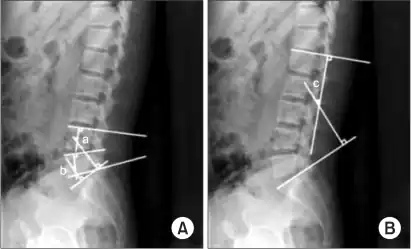

-

a,b)Cobb's angle for segmental lordosis and whole lumbar lordosis -

X-ray of lumbar hyperlordosis

Measurement and diagnosis of lumbar hyperlordosis can be difficult. Obliteration of vertebral end-plate landmarks by interbody fusion may make the traditional measurement of segmental lumbar lordosis more difficult. Because the L4–L5 and L5–S1 levels are most commonly involved in fusion procedures, or arthrodesis, and contribute to normal lumbar lordosis, it is helpful to identify a reproducible and accurate means of measuring segmental lordosis at these levels.[16][17] A visible sign of hyperlordosis is an abnormally large arch of the lower back and the person appears to be puffing out his or her stomach and buttocks.

Precise diagnosis is done by looking at a complete medical history, physical examination and other tests of the patient. X-rays are used to measure the lumbar curvature. On a lateral X-ray, a normal range of the lordotic curvature of between 20° and 60° has been proposed by Stagnara et al., as measured from the inferior endplate of T12 to the inferior endplate of L5.[18] The Scoliosis Research Society has proposed a range of 40° and 60° as measured between the upper endplate of Th12 and the upper endplate of S1.[18] Individual studies, although using other reference points, have found normal ranges up to approximately 85°.[18] It is generally more pronounced in females.[18] It is relatively constant through adolescence and young adulthood, but decreases in the elderly.[18]